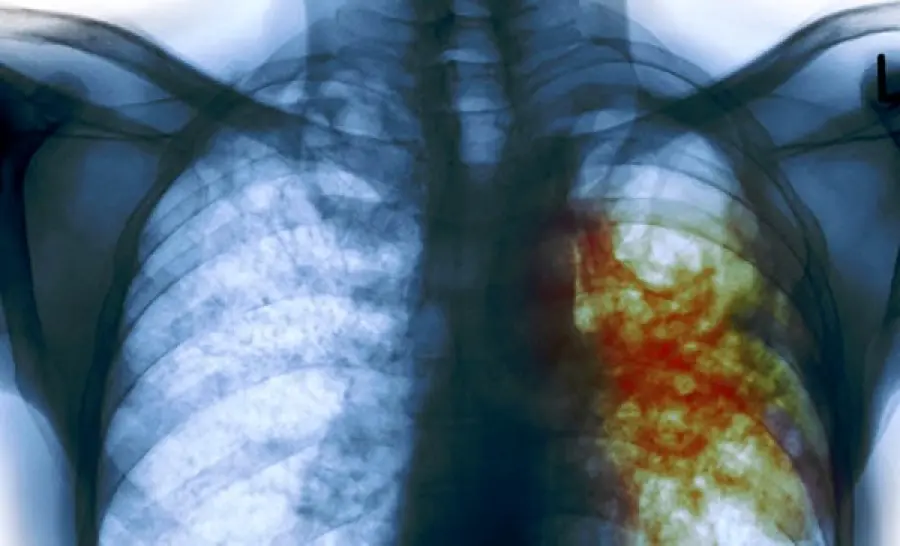

La tubercolosi si ripresenta in Italia. Moltissimi i casi registrati nei primi del 2018 solo a Bologna. Il bilancio sembra debba ancora salire-

Uno studio portato a termine dalla sede di Forza Italia in Emilia Romagna ha determinato un elevato numero di casi di tubercolosi incentrati, soprattutto, nella città di Bologna. Secondo quanto riportato da Il Resto del Carlino, a partire dal 2018 il numero dei pazienti affetti da tubercolosi è salito ben a 67. Si rende noto che questi 67 pazienti vengono seguiti distintamente in due diverse strutture sanitarie: 31 sono stati sposati dl Policlinico Sant'Orsola, mentre i restanti 36 vengono seguiti dalla Asl. Il numero di casi di tubercolosi formatisi in soli sei mesi dall'inizio del nuovo anno è davvero allarmante. Anche nello scorso anno i casi di tubercolosi registrati nelle due strutture ospedaliere è stato molto alto. Infatti si contano ben 104 casi presso la Asl e 89 al Sant'Orsola. La tubercolosi, che negli anni passati veniva diagnosticata in pazienti in maggior percentuali provenienti da altri paesi, in questi ultimi due anni viene contratta sempre più spesso anche da cittadini italiani. Infatti, nello scorso anno, dei 193 pazienti ai quali era stata diagnosticata la tubercolosi 35 erano italiani, mentre in questo nuovo alto la percentuale maggiore è per i pazienti italiani.La tubercolosi è la malattia più grave al mondo